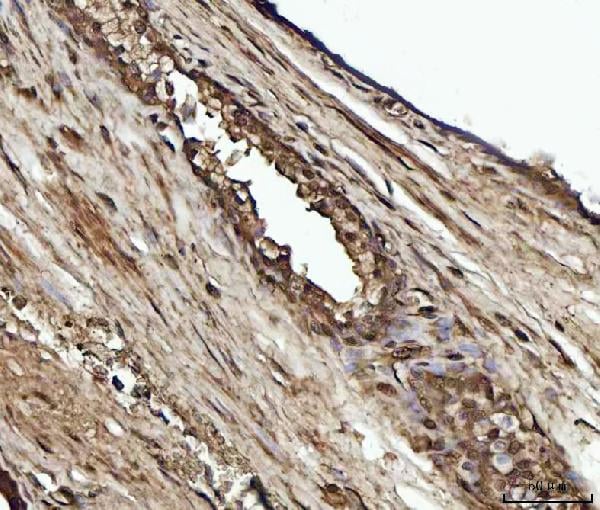

IHC (Immunohiostchemistry)

(Figure 2. IHC analysis of YWHAE using anti-YWHAE antibody (AAA126166).YWHAE was detected in a paraffin-embedded section of human lung cancer tissue. Heat mediated antigen retrieval was performed in EDTA buffer (pH 8.0, epitope retrieval solution). The tissue section was blocked with 10% goat serum. The tissue section was then incubated with 2 ug/ml rabbit anti-YWHAE Antibody (AAA126166) overnight at 4 degree C. Peroxidase Conjugated Goat Anti-rabbit IgG was used as secondary antibody and incubated for 30 minutes at 37 degree C. The tissue section was developed using HRP Conjugated Rabbit IgG Super Vision Assay Kit with DAB as the chromogen.)